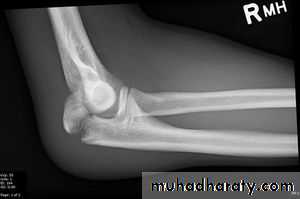

X-RAY; check the position of the radial head.

Treatment;Type1 splint.

Type2 displaced ORIF. (K wire & tension band wiring).